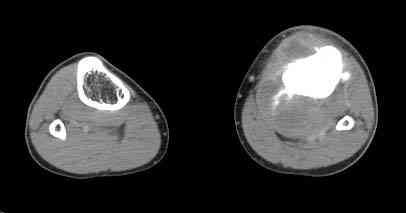

При обращении к нам произведена сцинтиграфия скелета - зоны гиперфиксации РФП: верхняя треть голени- 960%, нижняя треть бедра - 380%, Дистальный метафиз голени и затылочная область - 140%. В легких - метастазов нет. Произведена КТ (картинки в приложении). Учитывая абсолютную нестыковку рентгенологических и морфологических данных повторно биопсия. Выявлено, что первичная биопсия выполнялась из поверхностной параоссальной зоны - там локализованы хрящеподобные массы, далее очень плотная кость без хрящевых участков - биоптат взят фрезой с большим трудом. Морфологического заключения пока нет. Хотелось бы узнать Ваши варианты диагноза и соответственно тактику.